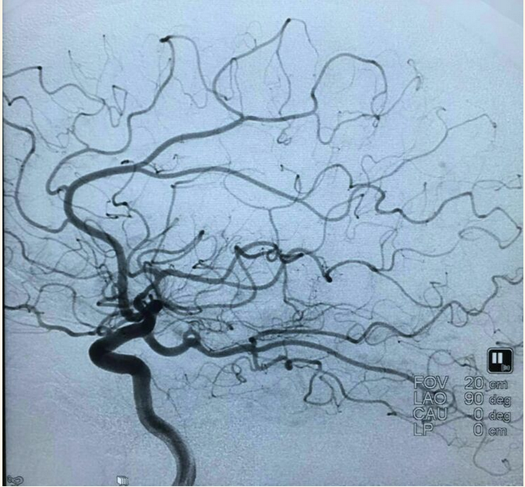

支架打开后:

最后造影:

术后第二天查看患者无不适,言语流利,四肢肌力5级,精神状态好转。继续双抗治疗。